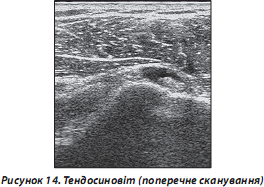

— сухожилля з СО: потовщені, їх ехоструктура, як правило, не змінена, в більшості випадків спостерігаються явища тендосиновіту (наявність анехогенної ділянки, обмеженої контуром СО, — рідини, що свідчить про запальний процес vaginae tendinum) (рис. 14);